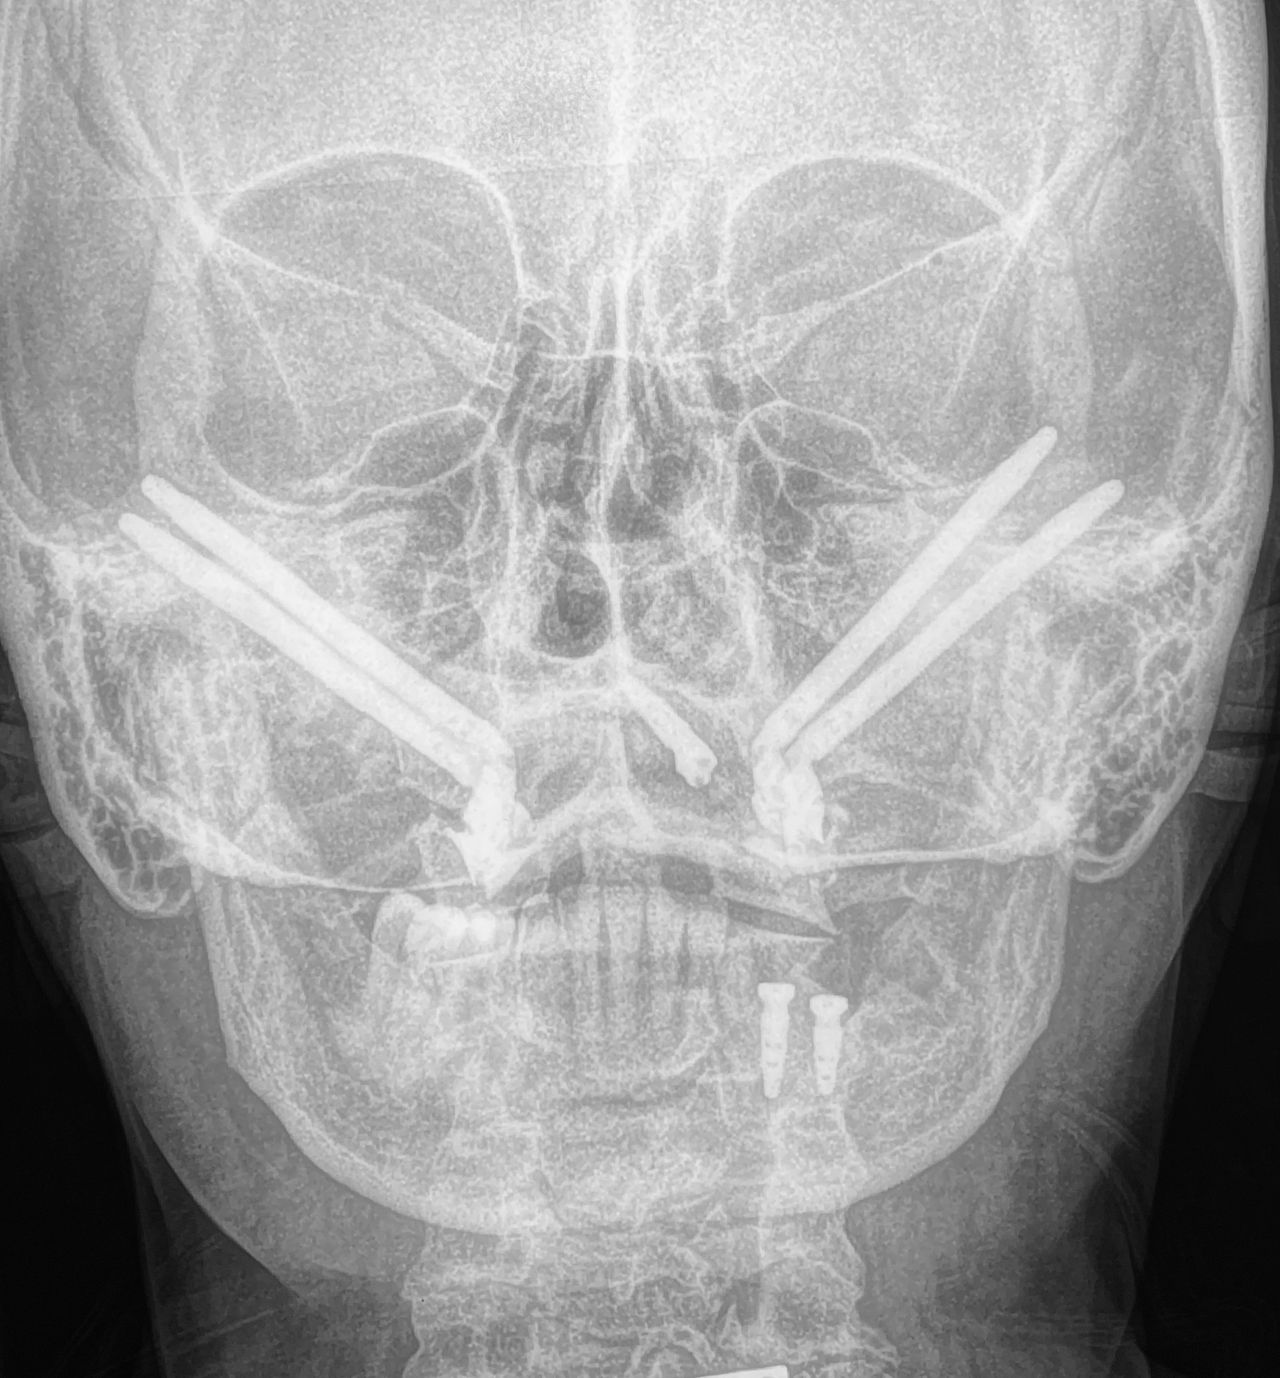

Cuento con experiencia en procedimientos de cirugía oral como: exodoncias simples, exodoncia de dientes incluidos y terceros molares, biopsias, frenillectomias, implantes dentales, implantes cigomáticos, implantes yuxtaoseos, regeneración ósea y tisular guiada.

En el área de cirugía maxilofacial tengo experiencia en el manejo quirúrgico de trauma facial, anomalías dento-faciales, disfunción de articulación temporomandibular, reconstrucción de maxilares, Cirugía estetica Facial, blefaroplastia, otoplastia, mentoplastia, Lifting facial, Lip Lift y reposicionamiento labial, retiro de biopolimeros en cara y Armonización Oro-Facial.

I have experience in oral surgery procedures such as: simple extractions, extraction of impacted teeth and third molars, biopsies, frenectomies, dental implants, zygomatic implants, juxta-osseous implants, and guided bone and tissue regeneration.

In the field of maxillofacial surgery, I have experience in the surgical management of facial trauma, dentofacial anomalies, temporomandibular joint dysfunction, mandibular reconstruction, facial cosmetic surgery, blepharoplasty, otoplasty, mentoplasty, facelifts, lip lifts and lip repositioning, removal of facial biopolymers, and orofacial harmonization.

- Cirugía ortognática